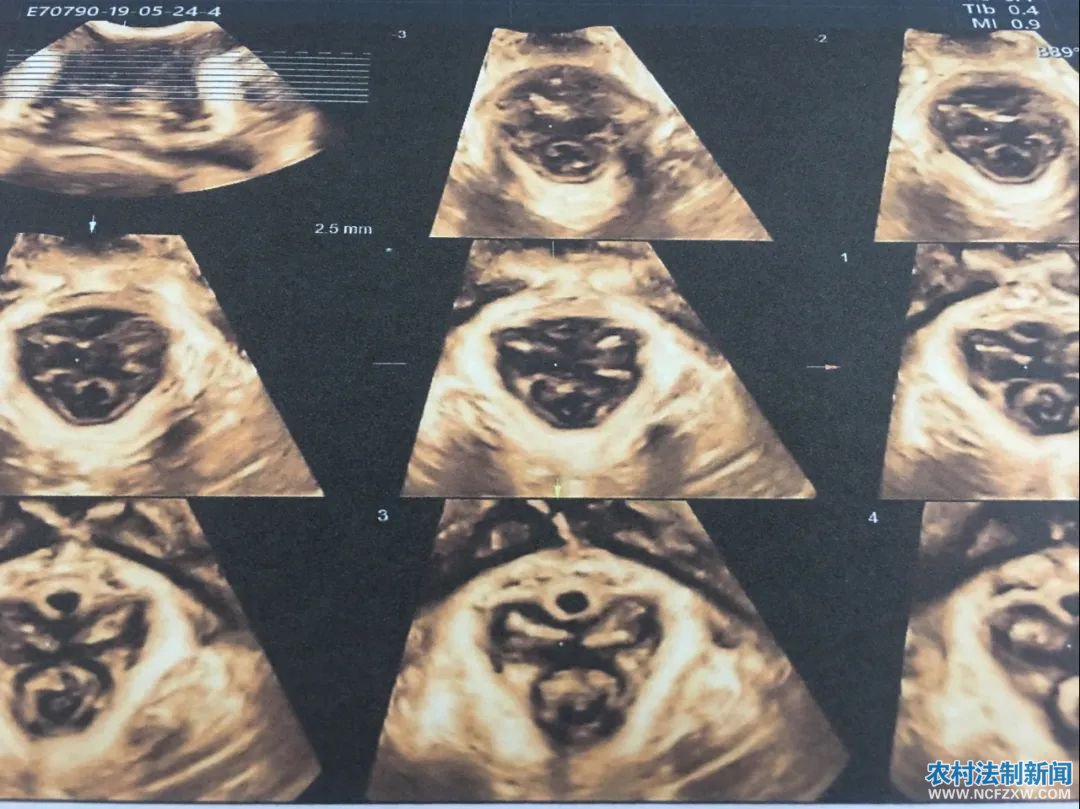

对于盆底肌撕裂等功能异常出现的压力性尿失禁、膀胱膨出、子宫脱垂等疾病,实时三维盆底超声检查能够做出准确诊断,并且具有安全无辐射、无痛苦等优点,是目前国内外了解盆底状态的重要检查方法。

可疑盆底功能障碍的人群均应行盆底超声检查,建议产后42天产妇及围绝经期女性均应行盆底超声筛查。盆底超声检查可作为产后常规筛查手段,一般于产后42天进行。检查要求:非月经期,检查当日排空大便(有便秘者可于前一日口服缓泻剂)。

盆底实时三维超声检查优势

通过盆底超声检查我们能早期发现、早期诊断盆底功能障碍性疾病,在临床症状出现前或症状较轻时通过物理治疗(盆底肌锻炼、生物反馈治疗)来恢复盆底支持结构的功能,避免或延缓手术治疗,提高患者生活质量,同时减轻家庭和社会的医疗经济负担。让“小毛病”不再“大痛苦”。